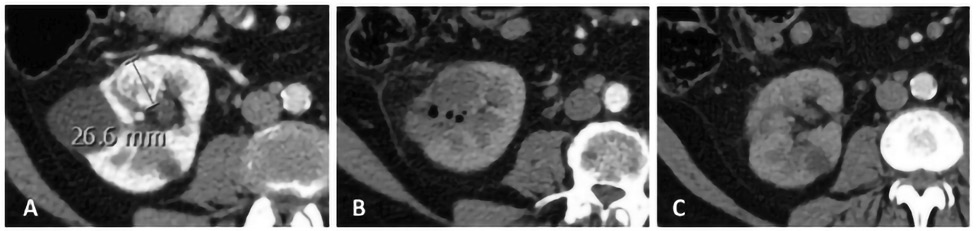

Після завершення процедури необхідно виконати контроль­ну КТ з внутрішньовенним контрастним підсиленням задля підтвердження повного покриття мішені та зони абляції. Одразу після процедури НОЕ абляційна ділянка виглядає як гіпоатенуйована зона, яка чітко корелює із зоною загибелі клітин. Поширеними знахідками є бульбашки газу, скупчення рідини і кільце гіпоатенуації на периферії зони абляції. Це кільце корелює з гребенем реактивної гіперемії, який зникає через близько 1 міс, і його не слід плутати із залишковою пухлиною. Радіологічні знахідки необхідно корелювати з клінічною картиною з метою диференціації типових післяопераційних змін та можливих ранніх післяопераційних ускладнень. Одразу після процедури зона абляції може виходити за межі початкової пухлини. З часом характерне значне зменшення початкового об’єму абляції; запально-набрякові зміни зменшуються, відбувається очищення від клітинних залишків, чому сприяє збережена васкуляризація. Зменшення до 1/3 початкового об’єму можна відмічати за 6–12 міс. У деяких випадках початкову зону новоутворення стає важко ідентифікувати на пізніх візуалізаційних контрольних дослідженнях, навіть може фіксуватися деяка регенерація тканин (рис. 6).

Рис. 6. Фокальна терапія раку нирки за допомогою НОЕ: a) — кортикальна гіперваскулярна карцинома нирки, що проростає в нирковий синус; b) — після абляції виключені такі ускладнення, як кровотеча, тромбоз судин або сечова нориця (екскреторна фаза не показана); типові газові бульбашки і гіподенсна ділянка в зоні абляції; c) — КТ-контроль через 6 міс, відмічається «регенерація» ниркової паренхіми, що ускладнює ідентифікацію зони абляції [цит. за 15]